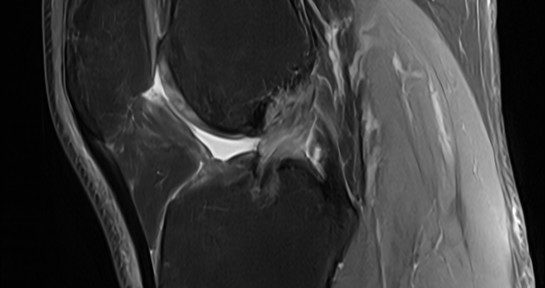

ACL Tear Natural Healing Case Report #50Case 50 | Natural Healing of Complete ACL Rupture: From Severe Ihara Type IV to Perfect Regeneration (ACLOAS Grade 0)

ACL Natural Healing Case Report #50: Most Severe Ihara …